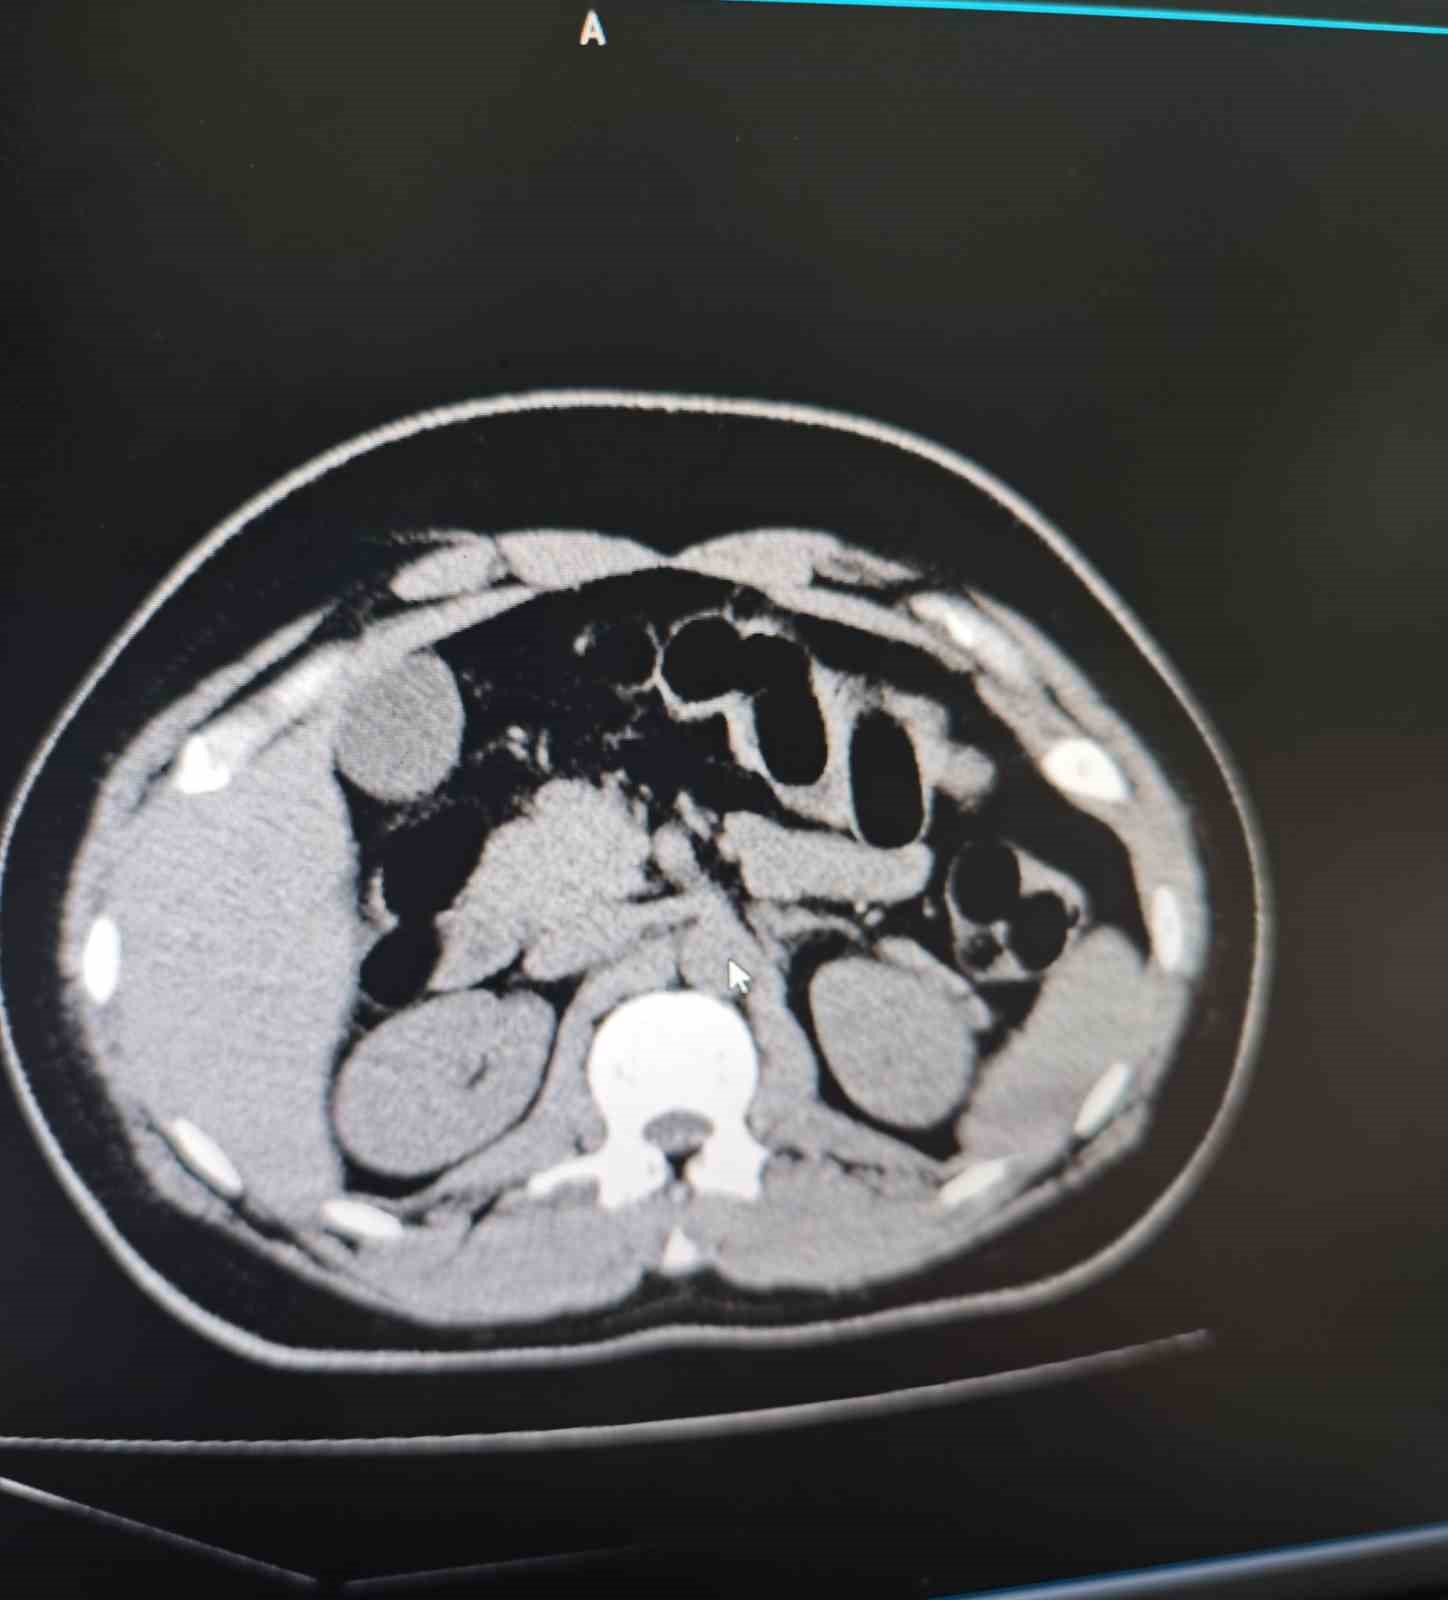

Muş Valiliğinden yapılan yazılı açıklamada, "Muş İl Emniyet Müdürlüğü Narkotik Suçlarla Mücadele Şube Müdürlüğümüz ekiplerince, ilimiz ve Batı illerine yönelik uyuşturucu madde sevkiyatının önlenmesine yönelik yürütülen risk analizi çalışmaları sonucunda, bir şüphelinin uyuşturucu madde taşıdığı değerlendirilmiştir. 25 Aralık 2024 tarihinde saat 02.20’de, şüphelinin bulunduğu şehirlerarası yolcu otobüsü, ekiplerimizce il merkezine girişte oluşturulan kontrol noktasında durdurulmuştur. Otobüste yolcu olarak bulunan S.S. isimli şahıs, görevlilerimizin sorgulaması sonucunda şüpheli görülerek hastaneye sevk edilmiştir. Hastanede yapılan iç beden muayenesi ve tomografi görüntüleri sonucunda, şahsın midesinde uyuşturucu madde taşıdığı tespit edilmiştir. Hastanede yapılan tespit sonrasında şüpheli şahsın midesinden toplam 84 adet kapsül içerisinde daralı ağırlıkları 842 gr gelen eroin maddesi ele geçirilmiştir. Şüpheli şahıs, ’Uyuşturucu ve Uyarıcı Madde Ticareti’ suçundan gözaltına alınmış, işlemlerinin ardından adli makamlara sevk edilmiş ve tutuklanmıştır. Uyuşturucu ile mücadelemiz kararlılıkla devam etmektedir” denildi.